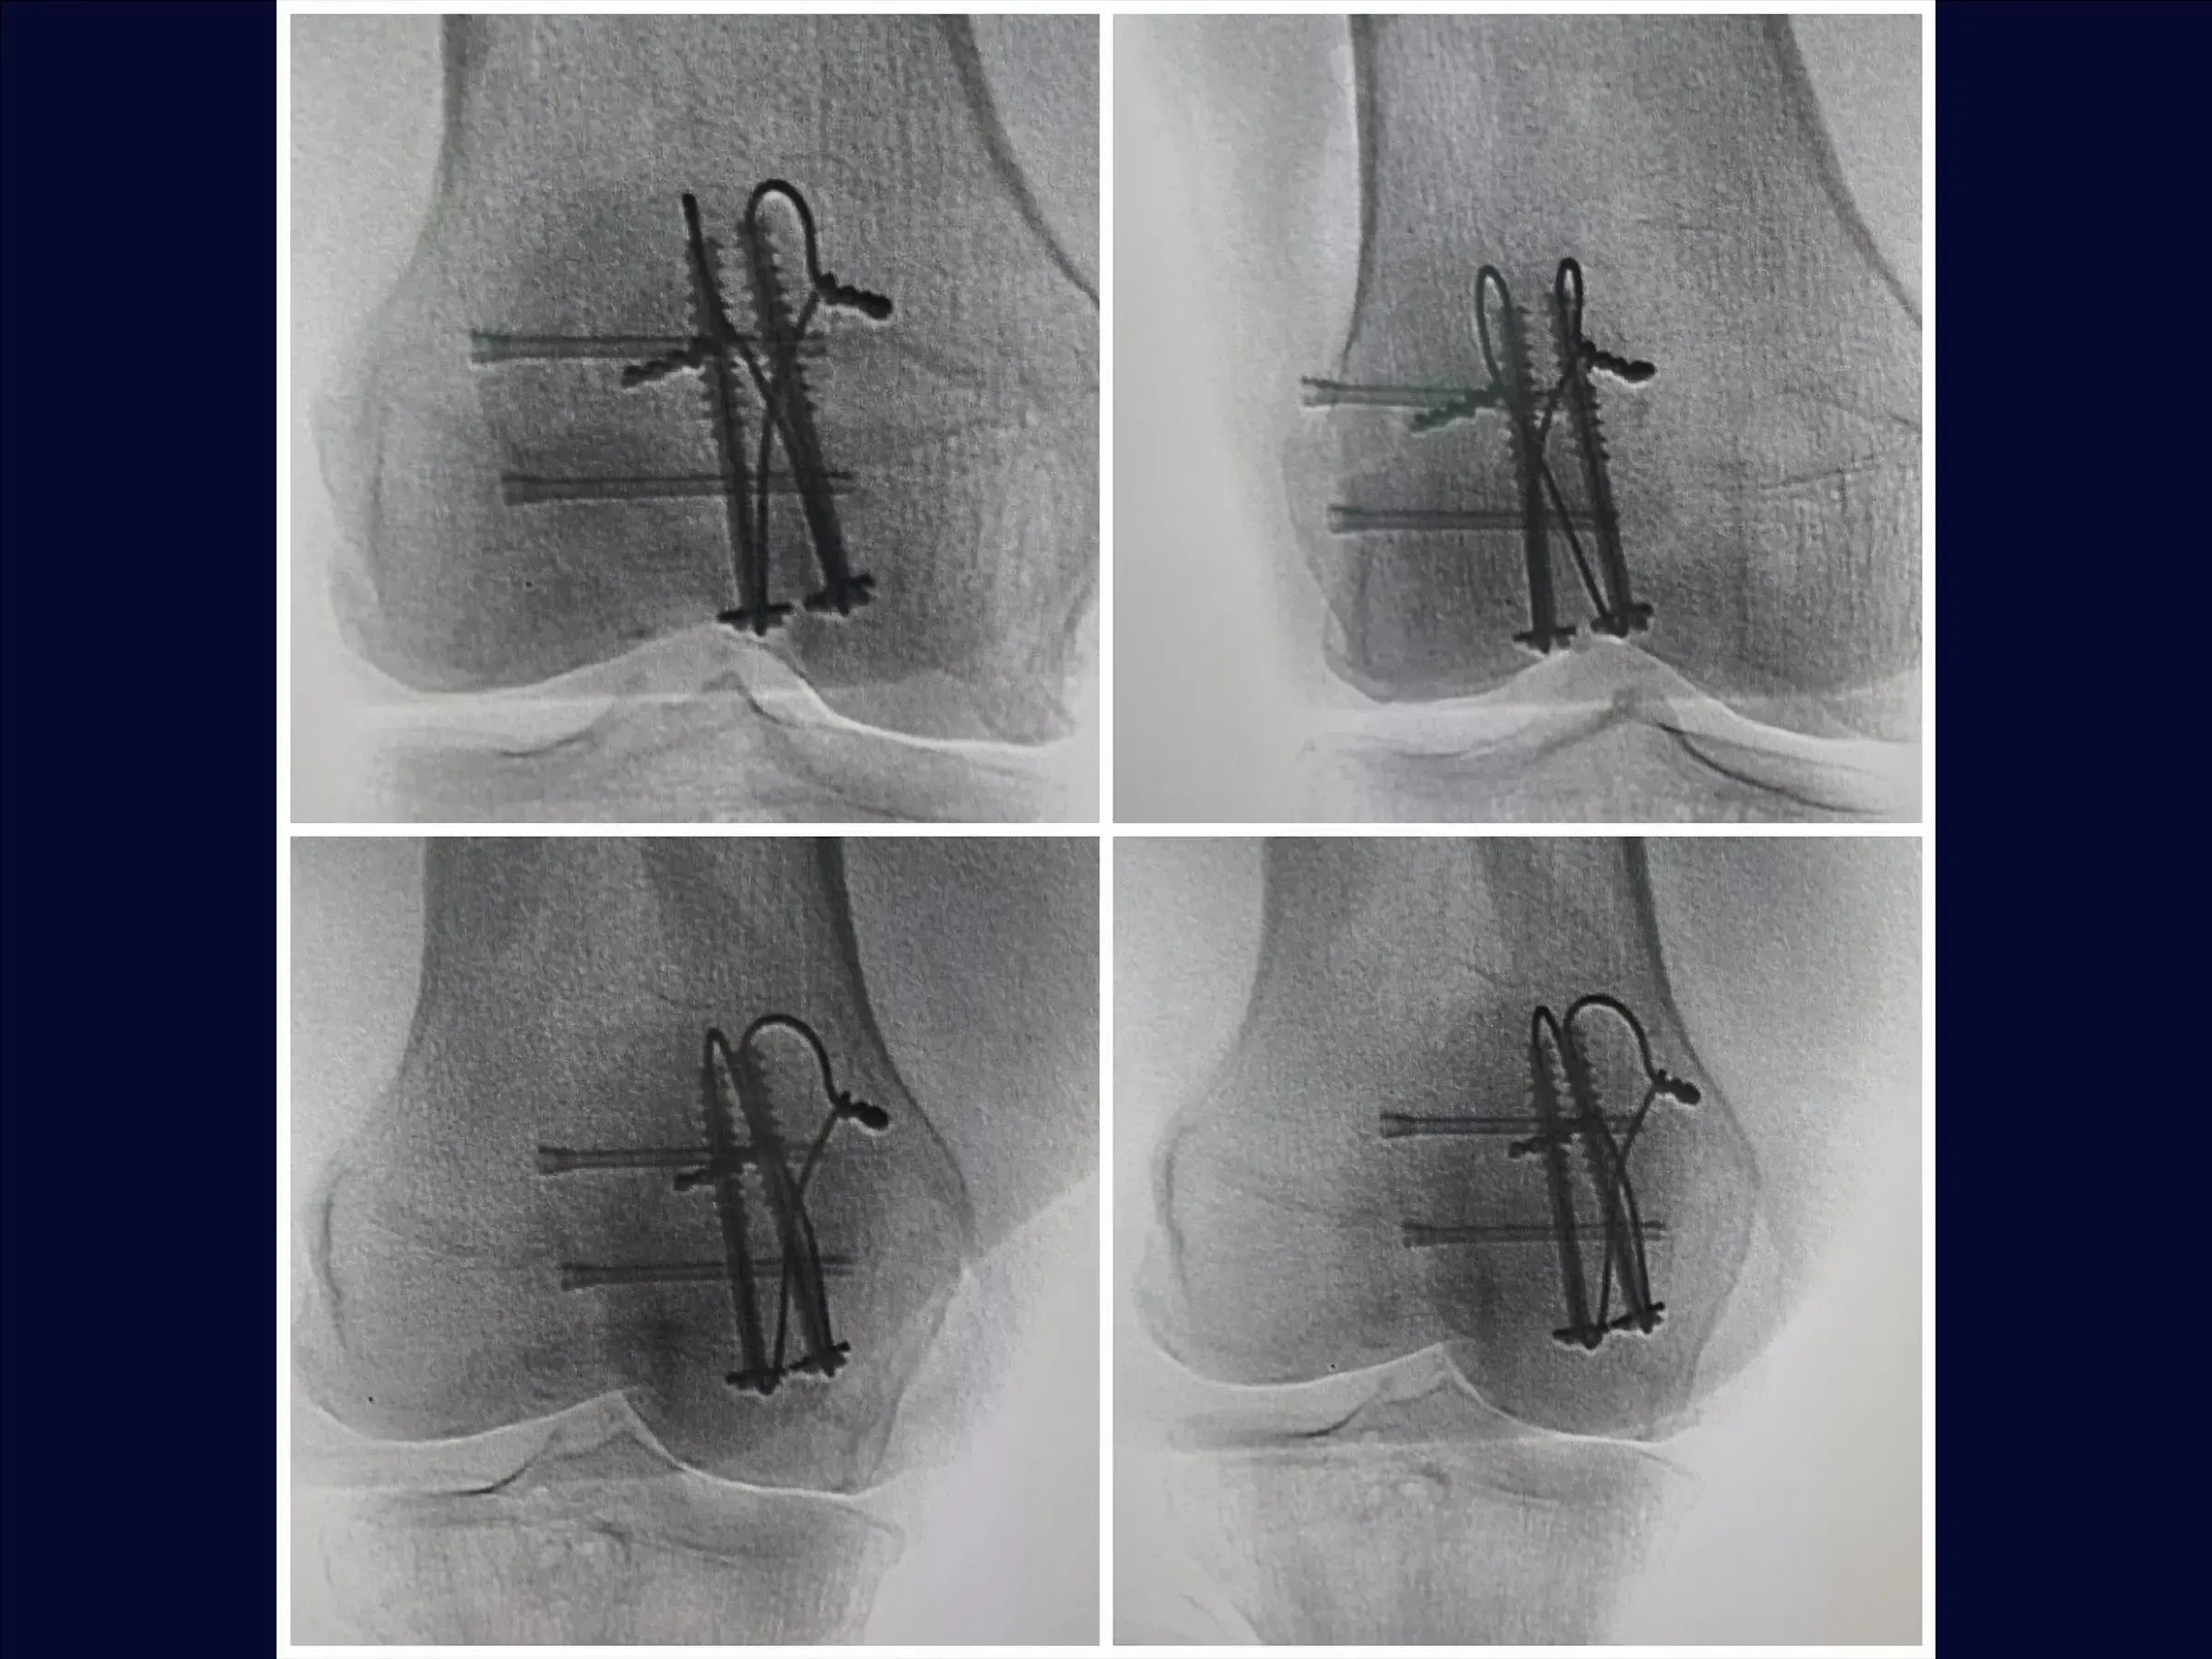

- Uso de parafusos canulados e cerclagem.

- Técnica de Redução Precisa: Metodologia para utilizar a pinça de redução e a mão como molde, ajustando a ancoragem para estabilidade primária sem translação.

- Aplicação de Cerclagem Eficaz: Confecção de incisões longitudinais no tendão quadricipital para posicionamento justo do fio ao osso, com técnica de tração e sepultamento das pontas na massa muscular para evitar complicações.

- Fixação de Fragmentos Laterais: Utilização de parafusos de dupla compressão para fixação de fragmentos na aleta lateral, com sepultamento completo da cabeça para prevenir proeminência do implante.

- Prevenção de Complicações: Estratégias para evitar instabilidade pós-fixação e considerações sobre a proeminência de implantes, especialmente placas em patela, que frequentemente necessitam de remoção.